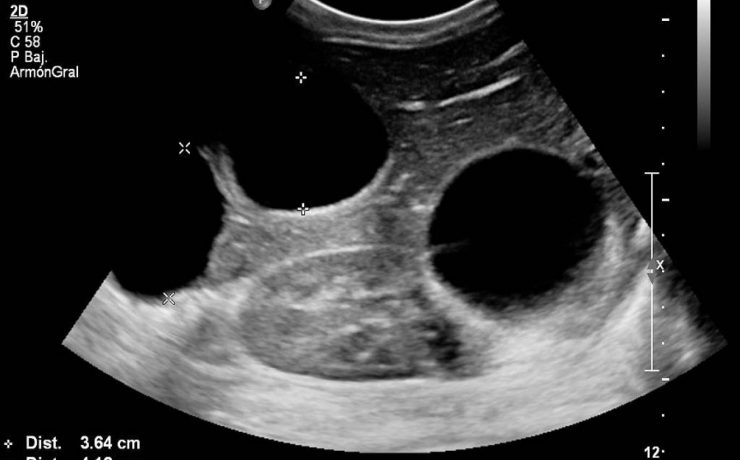

El onfalocele y la gastrosquisis son los defectos de la pared abdominal, de tamaño variable, que se ubica en directa relación con el cordón umbilical, que contiene asas intestinales y a veces otros órganos como parte del hígado, recubiertos por amnios en la superficie externa, peritoneo en la superficie interna,